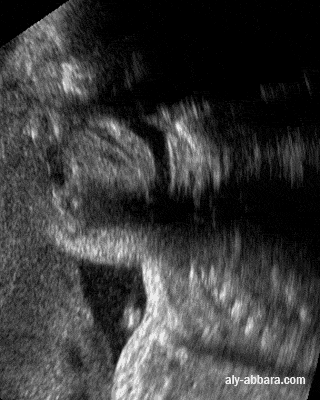

• Image échographique dynamique montrant une coupe sagittale passant par la cavité buccale et le pharynx, elle met en évidence la position anatomique et le rôle physiologique de la luette, un appendice charnu, mobile et contractile, prolongeant le bord postérieur du voile du palais et qui contribue à la fermeture du rhinopharynx pendant la déglutition.

• Fœtus de 32 semaines d'aménorrhée.